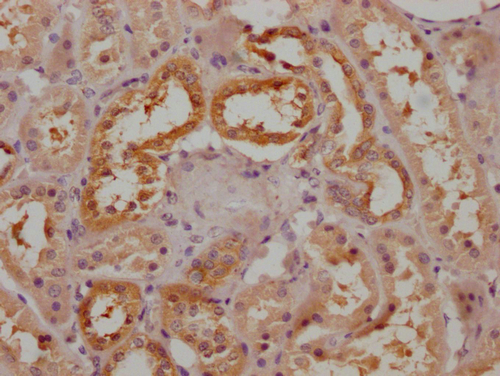

IHC image of PACO64977 diluted at 1:200 and staining in paraffin-embedded human kidney tissue performed on a Leica BondTM system. After dewaxing and hydration, antigen retrieval was mediated by high pressure in a citrate buffer (pH 6.0). Section was blocked with 10% normal goat serum 30min at RT. Then primary antibody (1% BSA) was incubated at 4°C overnight. The primary is detected by a Goat anti-rabbit polymer IgG labeled by HRP and visualized using 0.05% DAB.